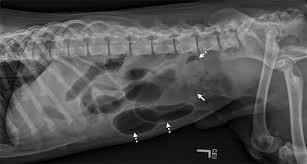

Intestinal Blockage

intestinal blockage in a dog

Intestinal blockages occur when foreign objects become stuck in the digestive tract. Dogs may swallow items such as toys, bones, socks, or other objects that cannot pass through the intestines.

Symptoms may include:

• vomiting

• abdominal pain

• inability to pass stool

• lethargy

• loss of appetite

Intestinal obstruction is a serious condition that may require surgery.

• abdominal X-rays